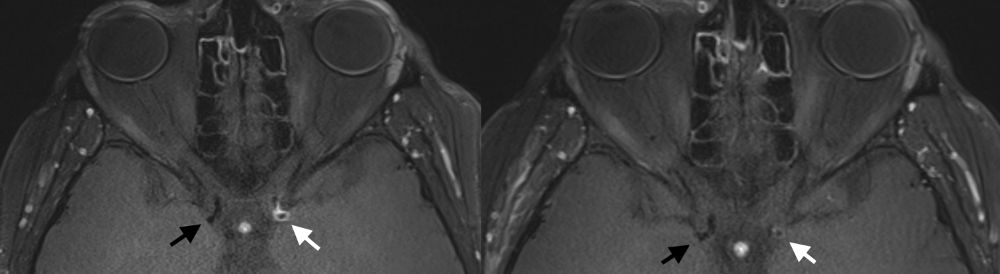

In der MRT Bildgebung fertigen wir neben den Routine-Sequenzen der Schlaganfalldiagnostik spezielle hochauflösende Sequenzen auf einem modernen 3 Tesla Gerät an, die mit einer Auflösung von unter einem Millimeter die betroffenen Gefäßwände darstellen können. So kann eine mögliche Aktivität und ein Voranschreiten der Erkrankung erkannt und dementsprechend die weitere Behandlungs- und Kontrollstrategie angepasst werden. Wir konnten als erste Gruppe weltweit beschreiben, dass sich die Kontrastmittelaufnahme der Gefäßwand mit einem zunächst an- und dann auch wieder absteigenden Prozess über rund 12-24 Monate verändert. In genau dieser Zeit verschließt sich das betroffene Gefäßsegment dann langsam. Diese Entdeckung ist von hoher Bedeutung für die Abschätzung des aktuellen Schlaganfallrisikos der Patientinnen und Patienten, zur Einordnung chronischer und akut voranschreitender Erkrankungen, sowie auch zum möglichen besseren Verständnis der Entstehung der Erkrankung. Denn hiermit hat man nun erstmals die Chance den aktiven Krankheitsprozess zu visualisieren und entsprechend der Aktivität in der Gefäßwand Biomarker zu untersuchen, die einen Rückschluss auf die Entstehung der Erkrankung zulassen.

MRT Aufnahme Gefäßwand der Halsschlagader

Hochauflösende MRT Aufnahme mit kräftiger Kontrastmittelaufnahme der Gefäßwand der Halsschlagader (weißer Pfeil), welche im Verlauf von wenigen Monaten deutlich abnimmt (Bild rechts ). Die Halsschlagader der Gegenseite (schwarzer Pfeil) zeigt jeweils keine Aktivität der Erkrankung.